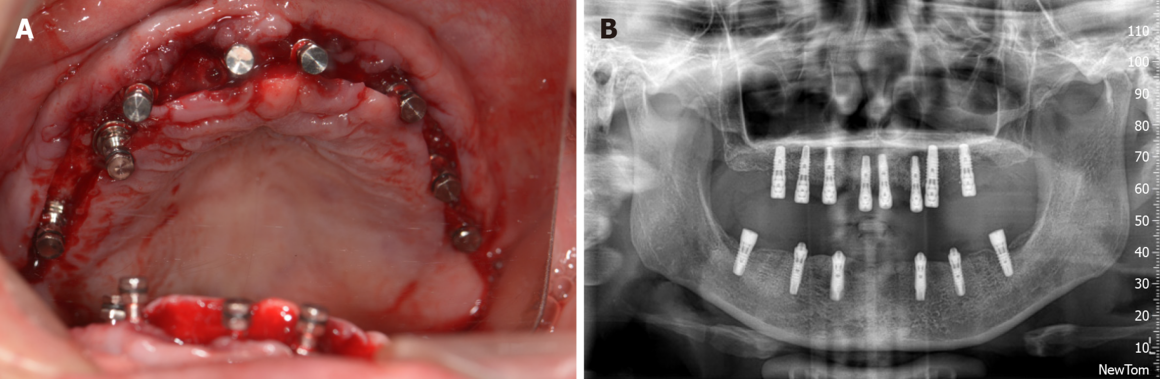

Тотальная реабилитация

Проблема: Отсутствие зубов